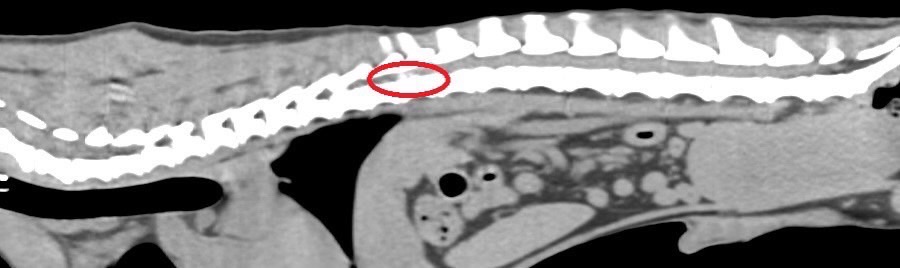

IVDD 定位病灶 擬定手術計畫

狗狗後腳癱瘓也有可能是血栓 不一定是骨骼神經肌肉問題喔

後肢癱瘓的柴柴經由他院轉診來築心做電腦斷層掃瞄因為狗狗以前病史有椎間盤突出問題

所以以為是脊椎問題想要來評估手術

掃瞄結果診斷為動脈血栓造成

主動脈血栓栓塞是一種急性且危及生命的疾病,當血液凝塊從心臟或其他部位脫落,經過血液循環流向並卡住動脈中的某些血管,造成局部的血液供應中斷、相應部位的器官或組織缺氧,將引起疼痛、損傷甚至壞死。

臨床上可藉由理學檢查、血液學檢查、超音波、電腦斷層等方式來確診犬主動脈血栓栓塞

此患犬在電腦斷層影像以及後續追蹤的超音波下都可見明顯血栓影像